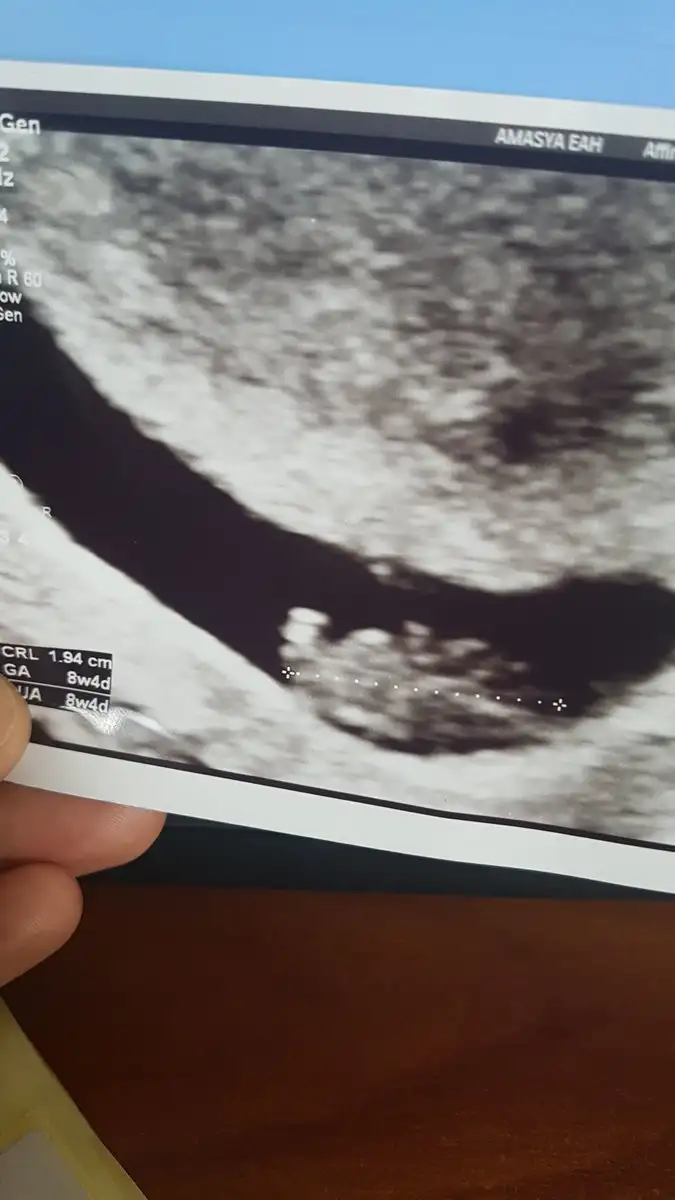

Bende denizlideyim hangi doktora gidiyorsunKızlar Günaydın. ..ben geldim çok şeyler yazildgindan kafam karışıyor ve bende mi anormallik var diye düşünmeden edemiyorum o yüzden sık girmiyorum artık. ..dün 7+6 da gittik ve altan çok şükür kalp atışını duyduk .çok sevindim .artık hamileyim elh..ben hamile olduguma inanmada güçlük çekiyorum da daha önce doğal yolla gebe kalmayıncaya. Rica etsem beni de ekler misiniz.